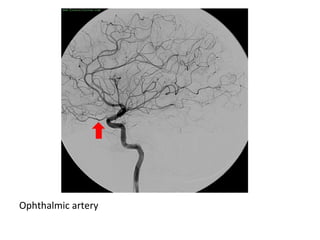

Ophthalmic artery

Lateral projection of a left common carotid artery injection that displays the

order of branching in the intracranial carotid including 1: ophthalmic , 2:

posterior communicating , 3: anterior choroidal and 4: anterior cerebral

arteries